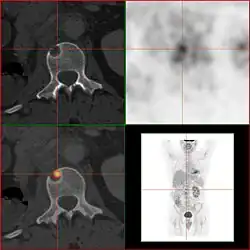

GLUT-1 ist das wichtigste Transportprotein für die Aufnahme von 2-FDG in Tumoren und normalem Hirngewebe. Die Aufnahme in der Skelettmuskulatur und im Herzmuskel ist durch Insulin stimulierbar und erfolgt über den GLUT-4-Transporter.[19] Das Enzym Hexokinase phosphoryliert 2-FDG anschließend innerhalb der Zelle. 2-FDG kann allerdings von den Zellen nach der Phosphorylierung nicht weiter verstoffwechselt werden. Die Rückreaktion, die Dephosphorylierung von FDG-6-Phosphat zu FDG, erfolgt in allen Organen – mit Ausnahme der Leber – und im Tumorgewebe sehr langsam.[19] Deshalb findet eine Anreicherung von FDG-6-Phosphat in den Zellen statt (metabolic trapping). Anhand des Zerfalls von 18F kann 2-FDG detektiert werden. Die Verteilung von 2-FDG im Körper erlaubt Rückschlüsse auf den Glucosestoffwechsel verschiedener Gewebe. Dies ist besonders für die frühe Diagnose von Krebserkrankungen von Vorteil, da eine Tumorzelle typischerweise aufgrund eines erhöhten Stoffwechsels viel Glucose verbraucht und dementsprechend 2-FDG anreichert.[20] Die Stoffwechselaktivität eines Tumors wird mit Hilfe des SUV-Wertes quantitativ beschrieben.

2-FDG wird in der PET für die Diagnose,[24] Staging (Stadienbestimmung), Therapieeinstellung und Therapiekontrolle verwendet. Man spricht in diesem Zusammenhang auch oft von der „FDG-PET“. 2-FDG ist als Diagnostikum eine außerordentlich nützliche und vielfach bewährte Verbindung. Die Anwendung hat einen rein diagnostischen Hintergrund. Genutzt wird dabei die bei der Paarvernichtung (Annihilation) von Positron und Elektron entstehende Vernichtungsstrahlung. Bei der Annihilation entstehen zwei hochenergetische Photonen, die eine Energie von 511 keV haben und in einem Winkel von 180 Grad zueinander, ausgesandt werden. Für die Therapie (Strahlentherapie, in diesem besonderen Fall würde man von einer Endoradiotherapie sprechen) sind die für die Diagnostik genutzten Gammaquanten nicht geeignet.

Für die FDG-PET gibt es drei Hauptindikationen für die Untersuchung von Patienten mit onkologischen Erkrankungen:[19] die Differenzierung zwischen benignen oder malignen (gutartig oder bösartig) Tumoren, das Tumorstaging bezüglich der Lymphknoten und Fernmetastasen sowie die Differenzierung Narbengewebe/vitales Tumorgewebe (Rezidiv, residueller Tumor). Die FDG-PET wird in der Onkologie zur Untersuchung von Lungenkrebs, dem kolorektalem Karzinom, Speiseröhrenkrebs, Magenkrebs, Kopf-Hals-Karzinom, Gebärmutterhalskrebs, Eierstockkrebs, Brustkrebs, dem malignen Melanom und den meisten Arten von Lymphomen eingesetzt.[31] Insbesondere sehr langsam wachsende Tumoren weisen in der Regel keine wesentlich erhöhte FDG-Aufnahme aus. Eine FDG-PET-Untersuchung ist dann meist nur in Ausnahmefällen sinnvoll.[19] Dazu gehören Prostatakarzinome, differenzierte neuroendokrine Tumoren (z. B. Karzinoid), bronchoalveoläre Karzinome, niedrig maligne Non-Hodgkin-Lymphome, niedrig maligne Hirntumore (Astrozytom II, Oligodendrogliom II) und das Leberzellkarzinom (vor allem höher differenzierte Formen). Entzündungen bzw. Heilungen zeigen neben dem Tumorgewebe ebenfalls eine erhöhte Stoffwechselaktivität und somit eine erhöhte FDG-Aufnahme. Eine Untersuchung zur Differenzierung beispielsweise von Abszessen und Tumorgewebe, Sarkoidose, Bronchialkarzinomen usw., kann deshalb mit 2-FDG kaum sinnvoll durchgeführt werden.[19]